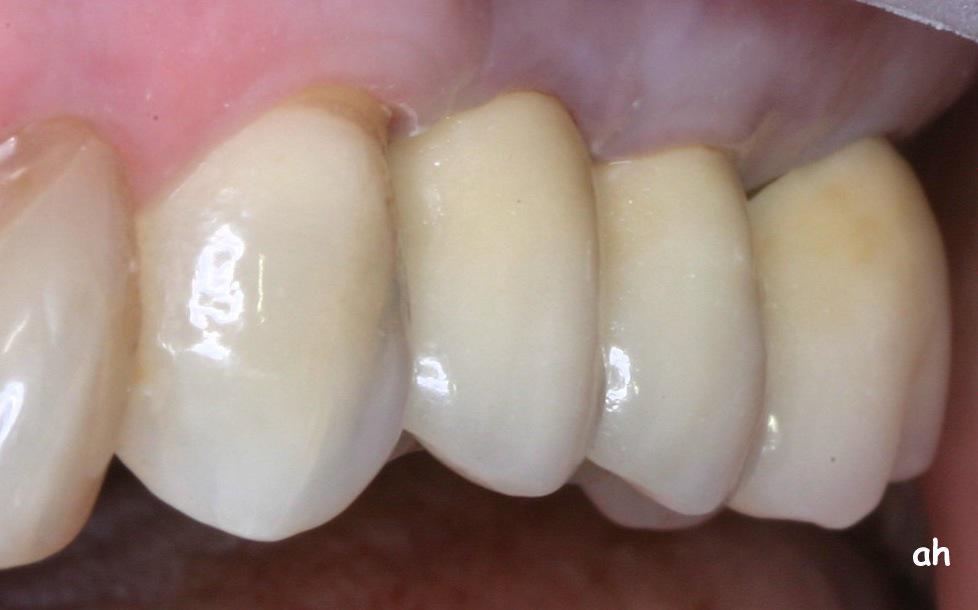

Exemple 12: Ici la pose de deux implants est envisagée, mais la hauteur d'os est insuffisante pour le deuxième implant. Le sinus (qui est une cavité creuse) est à moins de 6 mm de la surface de l'os. Idéalement il faudrait 10 mm d'os.

Exemple 12: Il faut donc relevé le sinus avec une greffe d'os avant de poser l'implant (Sinus lift).

Exemple 12: Les moignons vissés sur les implants 6 mois plus tard.

Exemple 12: Les couronnes en place.